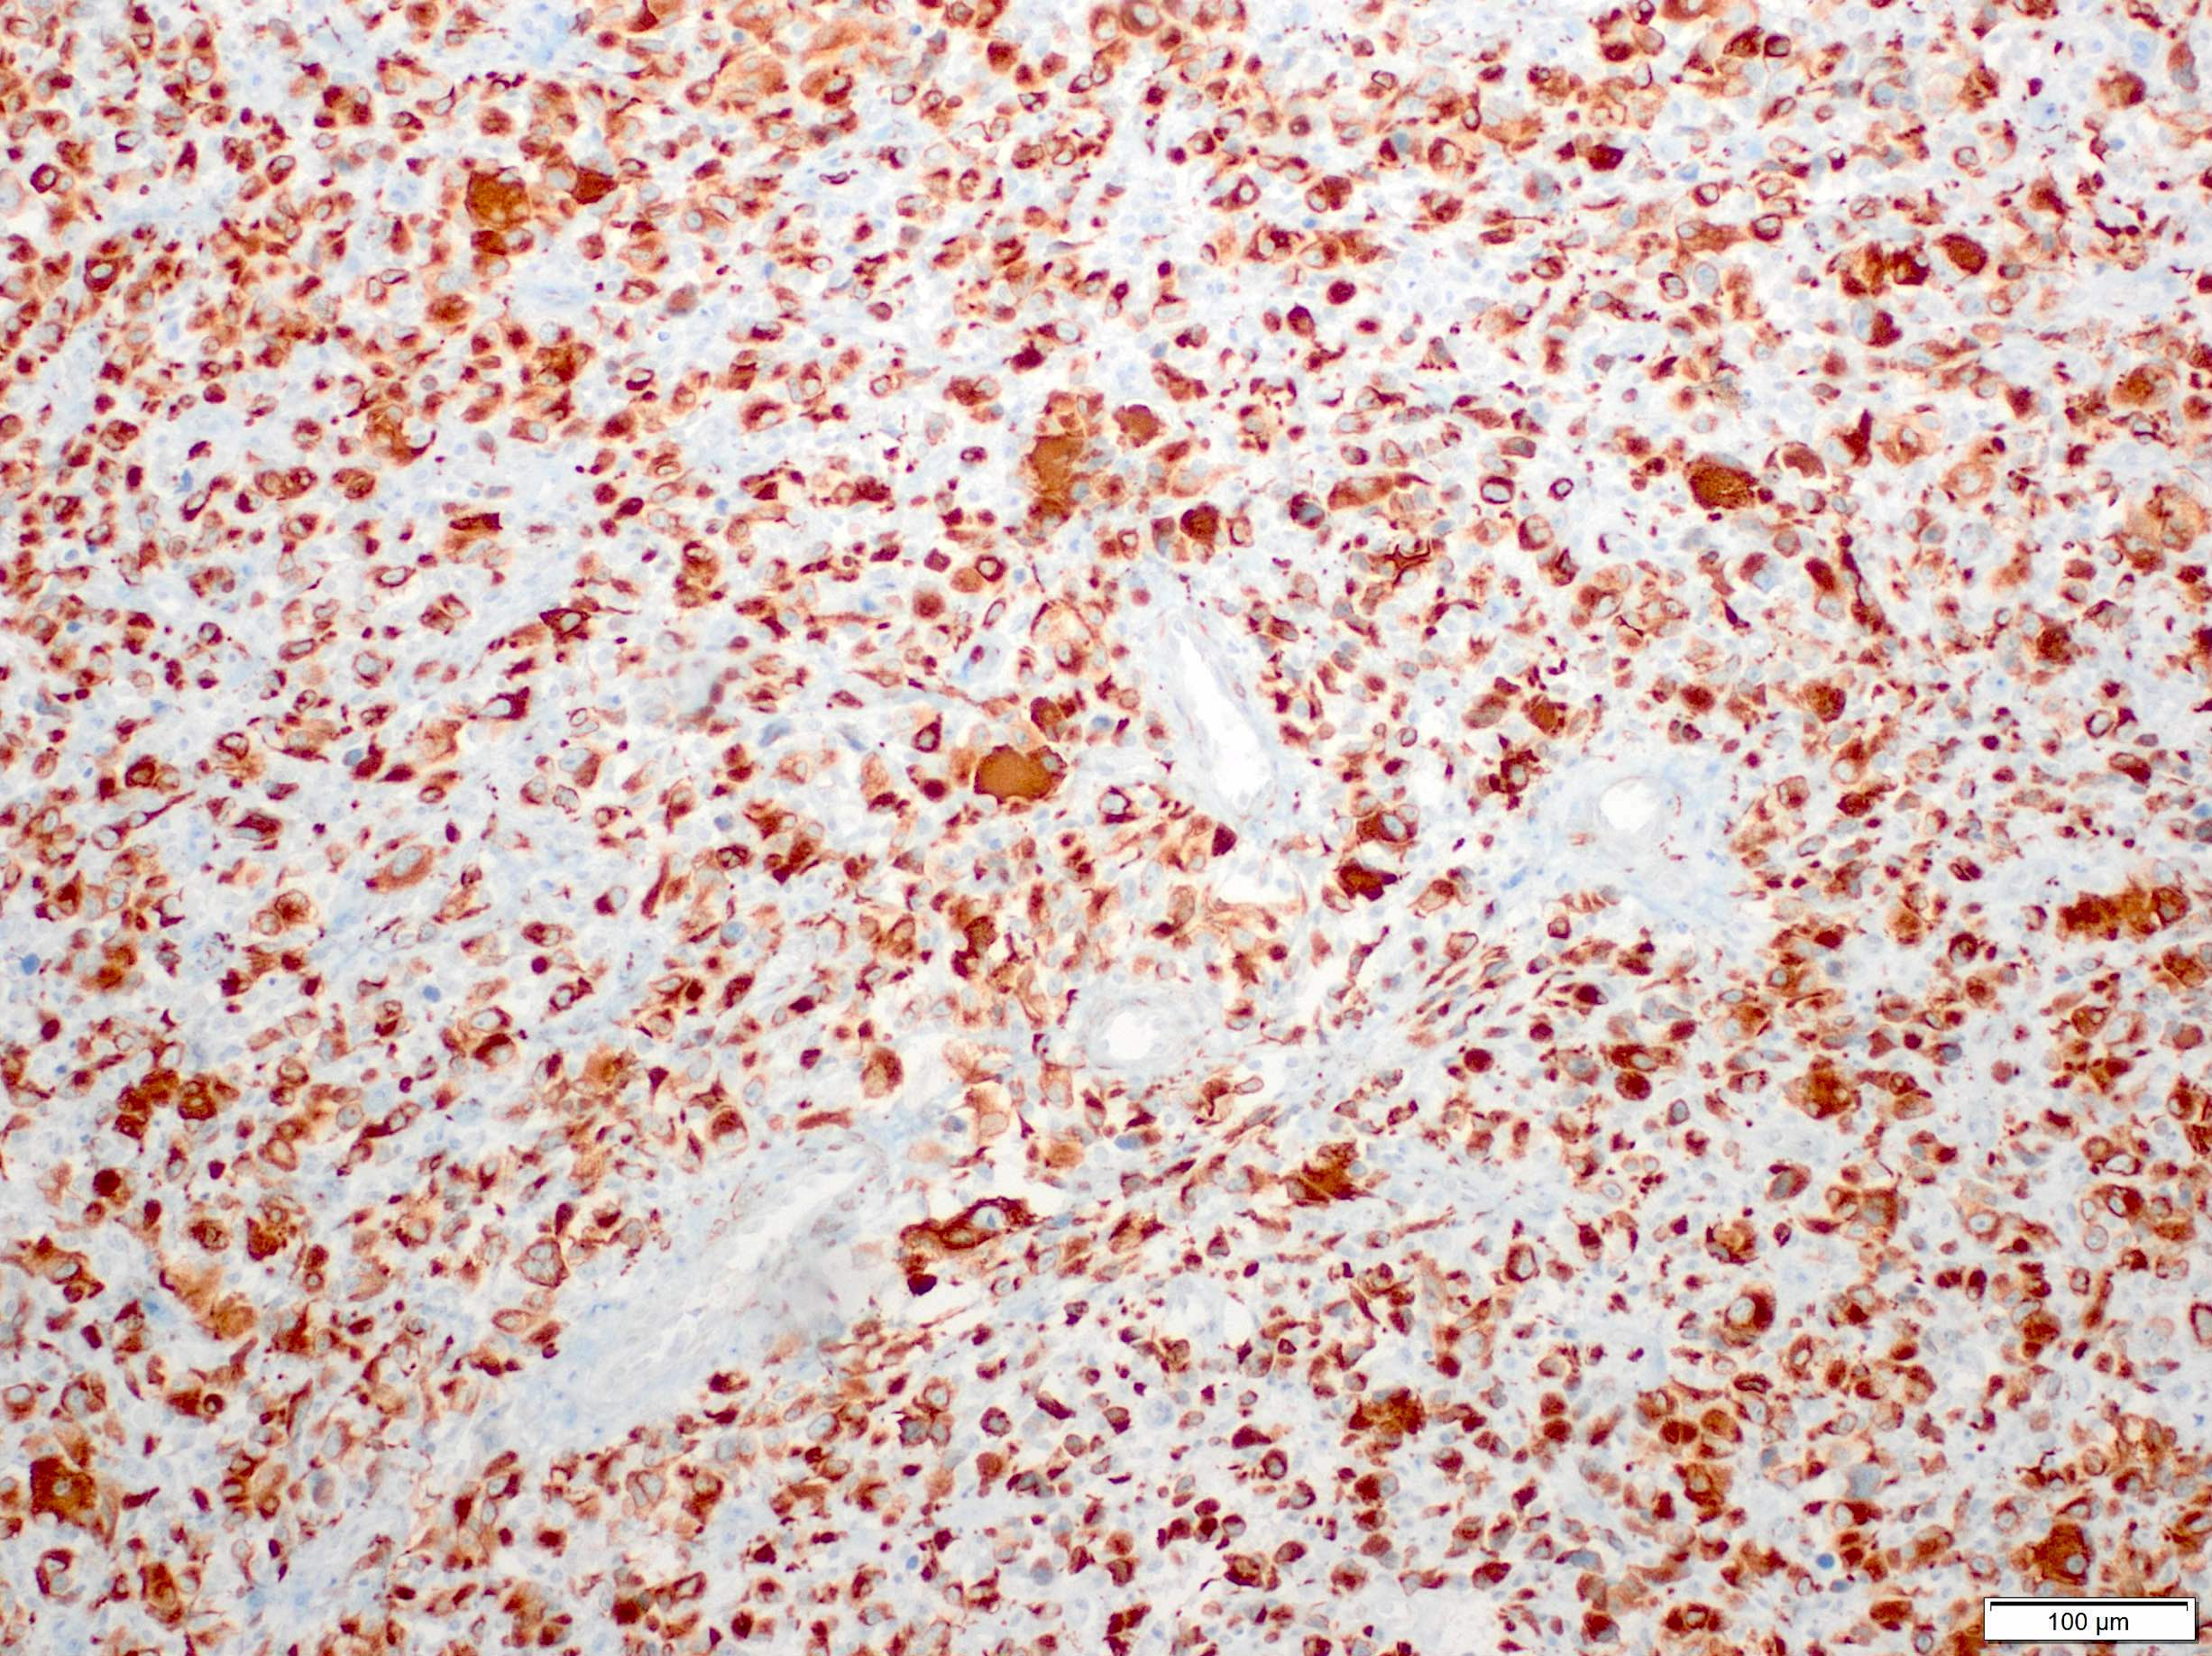

- High grade sarcoma composed of atypical cells that display skeletal muscle differentiation, confirmed with immunohistochemistry for myogenin or myoD1

- Skeletal muscle differentiation as confirmed by desmin, myogenin or MyoD1 (Ann Diagn Pathol 2018;36:50)

Positive stains

- Expresses desmin, MyoD1, skeletal muscle (fast) myosin and myogenin (Mod Pathol 2001;14:595)

- Variable SMA and may have focal keratin AE1 / AE3 and EMA positivity (Am J Surg Pathol 2009;33:1850)